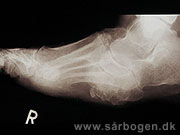

Charcot i mellemfod

Zoom

Charcot i mellemfod ...

Charcot i ankel

Charcot i ankel (rtg...